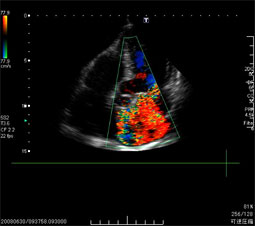

【エコー検査(超音波検査)】

頸動脈内部の血流測定    心臓の弁膜症の血流評価